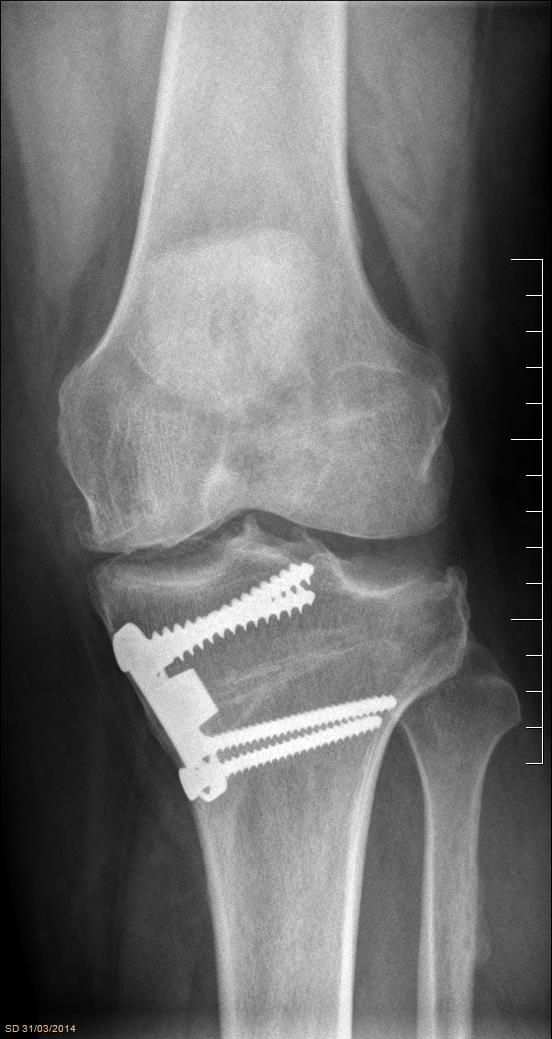

There are several surgical options described for osteochondral defects of the knee. The aim of our study was to analyze a series of patients treated with mosaicplasty with an average of 8 years follow-up.            Sixty-two patients with osteochondral defects of the knee who underwent mosaicplasties between 2001 and 2014 were included in the study with minimum follow-up of 2 years. Patients were evaluated using the Lysholm score, International Knee Documentation Committee Score (IKDC) and Kellgren-Lawrence radiographic scale.            Forty-five were men and seventeen women with an average age of 36 years old. Mosaicplasties were 45 in the medial condyle, 12 lateral condyle, 12 trochlea and 3 combined. Forty-two patients had isolated mosaicplasties and 20 patients presented associated surgical procedures (osteotomy, ACL reconstruction, meniscectomy). The mean results of the Lysholm score were 80.1 and IKDC was 66.7. There were no significant differences among the Lysholm and IKDC scores between these two groups. In 30 patients evaluated with radiography a satisfactory inclusion of the bony block was observed.            We believe that mosaicplasty is a procedure with a high degree of satisfaction with good functional results in patients with focal lesions of articular cartilage that may or may not be associated to other surgical procedures.